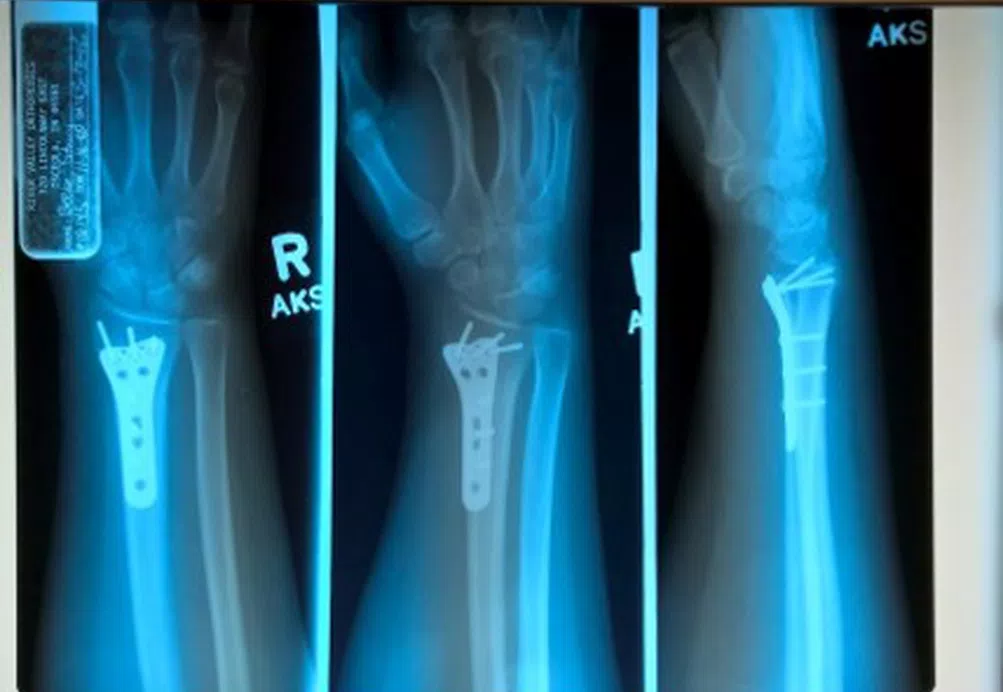

I slipped off my porch one night. I fell off the steps and my face hit the pavement so hard I couldn’t move. My wrist took the brunt of the fall. My husband helped me back up to my feet and I began to panic. He rushed me to the ER and I was taken to get X-rays. My wrist was broken.

I eventually was told I needed a plate and screws to hold my wrist together in order for it to heal properly. I figured that my wrist would heal and my life would go back to normal again. That is what is supposed to happen. But it didn’t. I woke up from surgery in so much pain I was screaming. The anesthesiologist immediately gave me a nerve block and numbed my arm. I thought that the pain would subside as the nerve block wore off, and the pain medicine kicked in, but that was not the case.